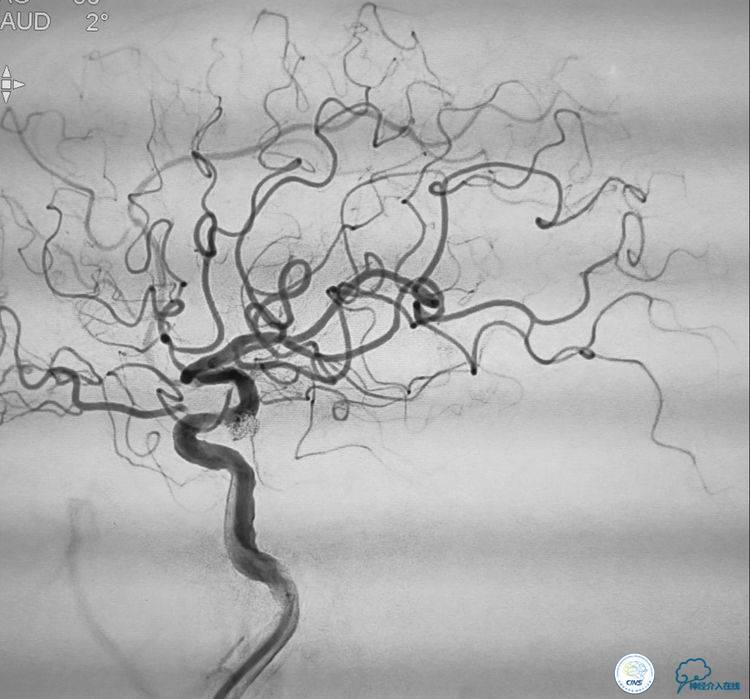

▼动脉瘤致密栓塞,血管狭窄改善,载瘤动脉通畅。

▼患者康复。

本例手术的特点和难点:髂动脉、主动脉、颈动脉迂曲,左侧颈动脉开口有狭窄。后交通动脉瘤呈宽颈分叶状,动脉瘤近端有一个约80一90%的狭窄。

治疗策略:采取支架辅助弹簧圈栓塞治疗动脉瘤。但由于动脉瘤近端的血管狭窄,如果不实施对狭窄血管的干预,支架释放后,很可能会导致支架打不开或者导致血管闭塞。因此首先对动脉瘤近端的狭窄血管进行球囊扩张,扩张的危险性就是有可能会导致动脉瘤的破裂。因此我们选用了超柔顺性的球囊。球囊扩张之后置入支架,由于动脉瘤呈分叶状,所以我们选择了双微导管支架辅助弹簧圈栓塞治疗这例动脉瘤,取得了良好效果。